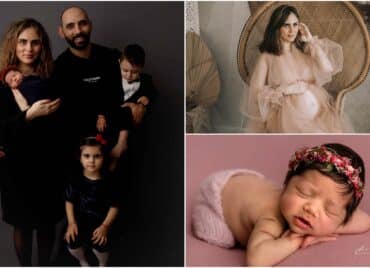

Corina a născut două fetițe gemene univiteline, obținute prin FIV. Surpriza extraordinară atât pentru părinți, cât și pentru medici a fost când au aflat că sarcina este una gemelară. Medicii și-au făcut treaba excelent, implantând un singur embrion, însă faptul că acesta s-a divizat în două a fost „mâna” divinității.

Conf. Dr. Romeo Micu, Medic primar OG, Expert în Fertilitate: „Specific la acest caz, am transferat un singur embrion. Întâmplarea și șansa pentru acest cuplu a fost ca acest embrion să se dividă, să se împartă în două și să rezulte două fetițe, în cele din urmă. (…)

Sarcina, fiind o sarcină gemelară monocorială biamniotică, ceea ce înseamnă că era o singură placentă și doi saci amniotici, a fost o sarcină care a evoluat, în principiu, în parametri fiziologici, până la un moment dat. Apoi a început să apară o diferență între cele două fetițe, diferență în dezvoltare. Este o situație care este relativ frecvent întâlnită în cazul sarcinilor monocoriale, cu o singură placentă și acest lucru ne-a determinat ca, la 36 de săptămâni, să decidem că este mai bine pentru fetițe să vină pe lume.”

Corina a născut două fetițe gemene univiteline, obținute prin FIV. La 36 de săptămâni de sarcină, fetițele au venit pe lume: „A fost cea mai fericită zi”

Corina Tamaș: „Nașterea a fost cea mai fericită zi. Nu cred că există o altă zi mai fericită decât în momentul în care îți vezi fetițele și le poți strânge în brațe, după atâtea încercări.”

Corina a născut două fetițe gemene univiteline, obținute prin FIV. Cele două fetițe au venit pe lume prematur la 36 de săptămâni de sarcină, însă au depășit prematuritatea fără niciun fel de probleme. Micuțele au fost îngrijite în secția de terapie neonatală a Spitalului Regina Maria din Cluj.

Dr. Sorin Andreica, Medic primar Neonatologie: „În secția de Terapie Intensivă Neonatală, cei mai mulți copii sunt născuți înainte de termen, deci copii prematuri. Prin urmare, echipamentele, infrastructura, personalul medical este pregătit pentru a primi astfel de copii prematuri. În momentul de față îngrijim copii născuți de la 32 de săptămâni de gestație. Confortul de îngrijire este cât se poate de bun atât pentru copil, cât și pentru părinți. Inclusiv tatăl poate să participe la aceste îngrijiri, prin urmare întreaga familie poate să fie implicată în îngrijirea unui copil înainte de termen.”